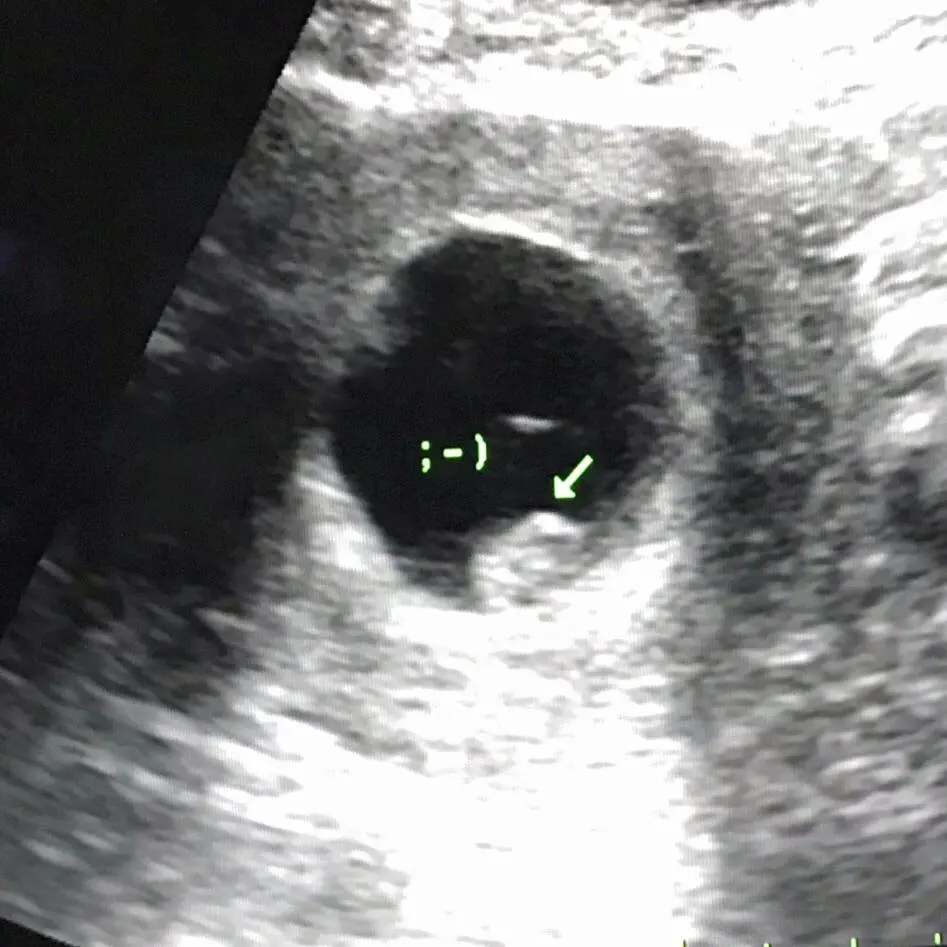

จากประสบการณ์การดูแลคนไข้ บ่อยครั้งผมได้ดูแลสตรีตั้งครรภ์ที่ประสบปัญหาตั้งครรภ์นอกมดลูก ซึ่งเป็นภาวะที่ค่อนข้างอันตราย และในคนไข้บางรายอาจโชคร้าย ความรุนแรงจากการเสียเลือดอาจนำไปสู่การเสียชีวิตเลยนะครับ

แต่ในบางกรณี ที่ตัวอ่อนฝังตัวในตำแหน่งอื่นที่ไม่ใช่ โพรงมดลูก ทางการแพทย์เรียกว่า การตั้งครรภ์นอกมดลูก ซึ่งตำแหน่งของการฝังตัวที่ผิดปกตินี้อาจจะเกิดที่ท่อนำไข่ ที่รังไข่ ที่เยื่อบุช่องท้อง ที่ปากมดลูก เป็นต้น ทั้งหมดนี้ถือเป็นการฝังตัวที่ ผิดที่ผิดทาง และทารกจะไม่สามารถเติบโตแบบทารกปกติทั่วไปได้นะครับ ,

เนื่องจากตำแหน่งที่ตัวอ่อนไปฝังตัวผิดที่ผิดทาง อวัยวะนั้นจะมีความบอบบาง ไม่สามารถขยายขนาดสำหรับการเติบโตของทารกได้ จึงมักเกิดการแตกหรือ การฉีกขาดของอวัยวะที่ตัวอ่อนไปฝังตัว จนทำให้คนไข้ตกเลือดในช่องท้องอย่างมากมาย

เนื่องจากยาคุมฉุกเฉิน มีผลทำให้ การบีบตัวของท่อนำไข่ และเส้นขนเล็กๆภายในท่อนำไข่ทำงานผิดปกติ ตัวอ่อนจึงเคลื่อนที่ไปยังโพรงมดลูกได้ช้ากว่าปกติ และการฝังตัวของตัวอ่อนมีเวลาที่จำกัด เมื่อถึงเวลาที่ร่างกายกำหนดต้องฝังตัวทันที ถ้าเคลื่อนที่ช้าตัวอ่อนจะไปไม่ถึงโพรงมดลูกตามธรรมชาตินะครับ ทำให้เมื่อถึงเวลาต้องฝังตัวตัวอ่อนฝังตัวในตำแหน่งที่ผิดปกติ พูดง่ายๆว่า ฝังตัวก่อนไปถึงที่หมาย หรือไปไม่ถึงดวงดาวก็น่าจะพอได้นะครับ